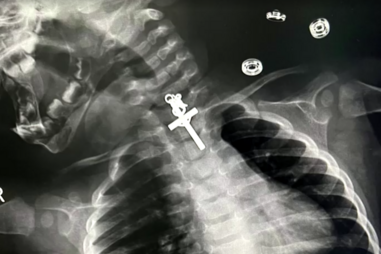

Pais falam em "milagre" e agradecem a profissionais de saúde.

14 de novembro de 2023 às 23:52